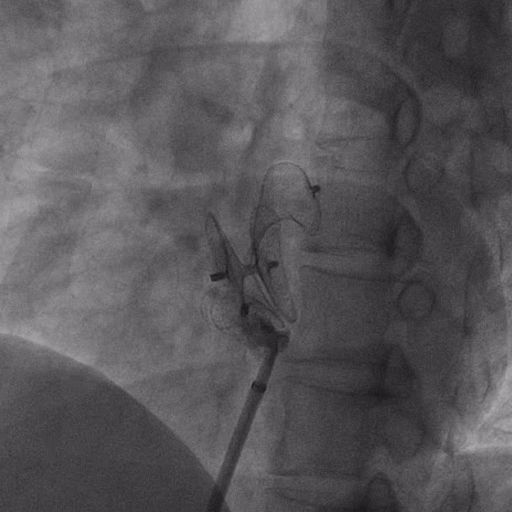

在獲得患者同意后,1月12日,尚福軍主任為患者進(jìn)行了PFO封堵術(shù)。術(shù)中造影可見封堵器殘余漏,尚福軍主任用精湛的技藝,順利通過封堵器殘余漏裂縫,將右心導(dǎo)管從右房送入左房,且順利到達(dá)肺靜脈;遂行卵圓孔未閉封堵術(shù)后殘余漏再次封堵;且完美釋放PFO封堵器,可見兩封堵器呈“馬蹄蓮”狀,再次術(shù)中造影未見殘余漏。

術(shù)后,小鞏生命體征平穩(wěn)。相關(guān)檢查顯示正常,且術(shù)后完善心臟彩超及發(fā)泡試驗,可見封堵器位置良好,未見右向左分流,發(fā)泡試驗陰性。